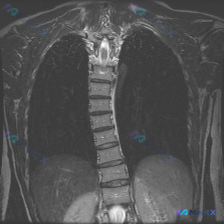

这张胸部MRI的胸椎形态有点特别,你会先考虑哪类侧弯?

整理了一份胸部MRI冠状位T2加权像的影像资料,几个点比较明确:

- 胸椎序列有明显的左凸侧弯,椎体序列走行弯曲

- 胸廓因为侧弯变得不对称,纵隔(心脏大血管)位置也有偏移

- 目前T2像上看脊髓信号还算均匀,肺野也没看到明显的渗出、结节或积液

但仅凭这一个序列,好像还不能直接定侧弯的性质——是特发性、退变性,还是得警惕其他问题?